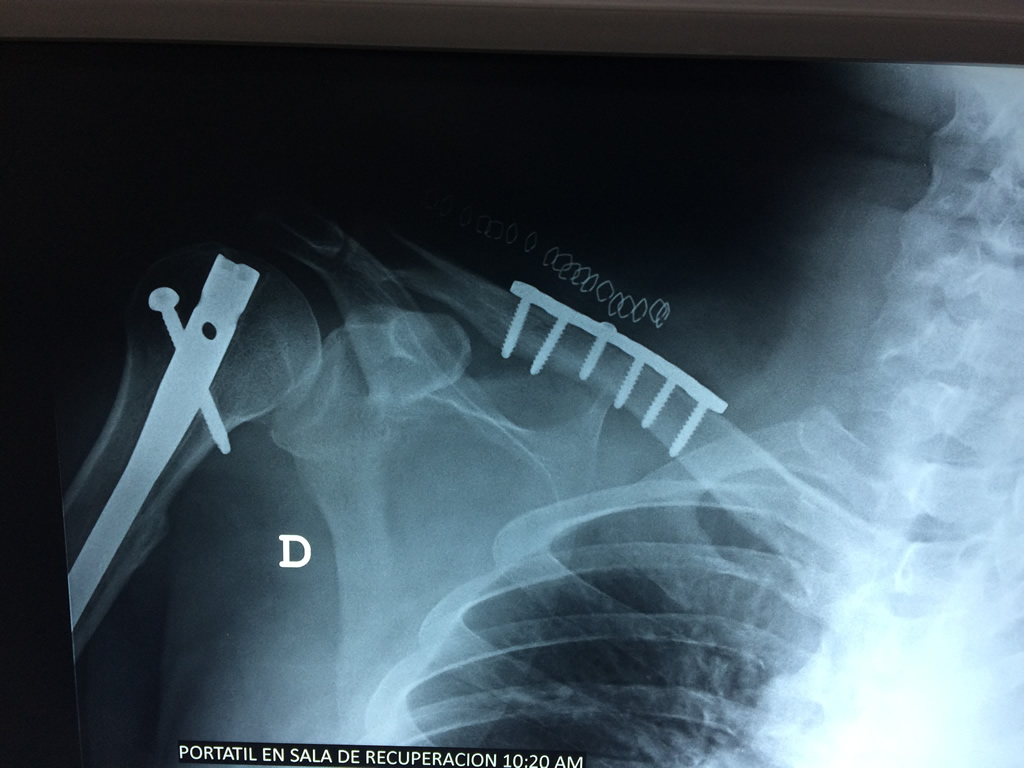

Cirugías de Codo - Clavícula

La clavícula es un hueso largo, con forma de "S" itálica, situado en la parte anterosuperior del tórax. Junto con la escápula forman la cintura escapular. Se puede palpar por toda su longitud y se extiende del esternón al acromion de la escápula, siguiendo una dirección oblicua lateral y posterior.